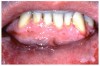

Fig 3. Topical ASA-induced Cytotoxic Reaction.

Figure 3

Stomatitis and ulcerative stomatitis represent cytotoxic reactions to topically applied agents, e.g., LAs; or may result from the systemic administration of cytotoxic drugs, e.g., antineoplastic agents, which damage not only tumor cells, but all rapidly dividing normal cell populations.14,16 The degree of tissue damage depends on the specific agent, dosage, dosage schedule, and patient-related variables. The lesions may appear as erythematous macules, patches, papules, plaques, or diffuse ulcerations (Figure 3 and Figure 4).